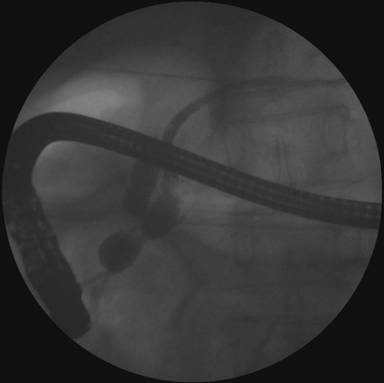

A 63-year-old male had two episodes of acute pancreatitis by biochemistry and abdominal ultrasonography. EUS findings showed an ampullary mass and cystic dilatation of terminal portion of duct of Wirsung suggestive of wirsungocele (Figures 1 and 2). EUS guided FNA from the ampulla suggested a neuroendocrine tumor. MRCP confirmed EUS findings of wirsungocele and ampullary mass (Figure 3). ERCP (Figure 4) and endoscopic ampullectomy was then performed and patient made an uneventful recovery. The histopathological examination and immunohistochemistry showed neuroendocrine tumor (pathological classification: G1) with cells expressing synaptophysin and chromogranin (Figure 5). The Mib proliferation index was less than 2%. The pancreatic duct was seen well dilated within the tumor tissue.

Figure 4. ERCP showing dilation of terminal part of pancreatic duct. |